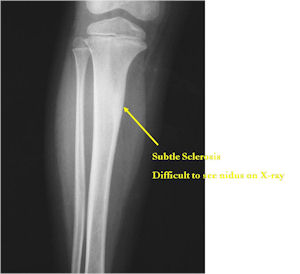

- Lucent nidus surrounded by a zone of marked sclerosis

- The nidus may demonstrate mineralization/ossification usually from the center outward that appears as a central zone of density within the nidus

- A nidus that is heavily ossified may blend in with the surrounding sclerosis and be difficult to detect on a plain x-ray.